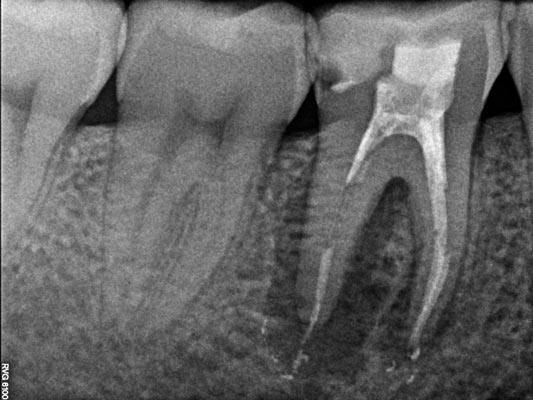

Imágenes: Endodoncia en un molar inferior izquierdo

Reendodoncia